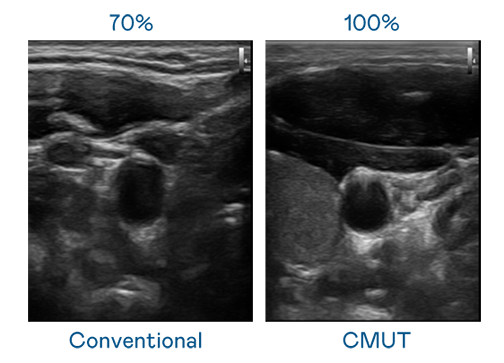

CMUT 技术是一种用电容式微机电元件来产生超音波讯号的技术。与传统 PZT 压电式技术相比,CMUT 频宽增加 30%,更宽频的超音波讯号让影像解析度大幅提升,是实现高影像品质医疗超音波扫描、促进精准医疗发展的关键技术。

大频宽带来超清晰影像

超音波影像的解析度高低,首先取决于探头能发出的讯号频宽。z6.com CMUT 可提供高清晰的超音波讯号,提供高频宽、高灵敏度、影像纹理细节更高的超音波影像,协助医护人员缩短影像判读时间及利用精准的医疗影像进行诊断。